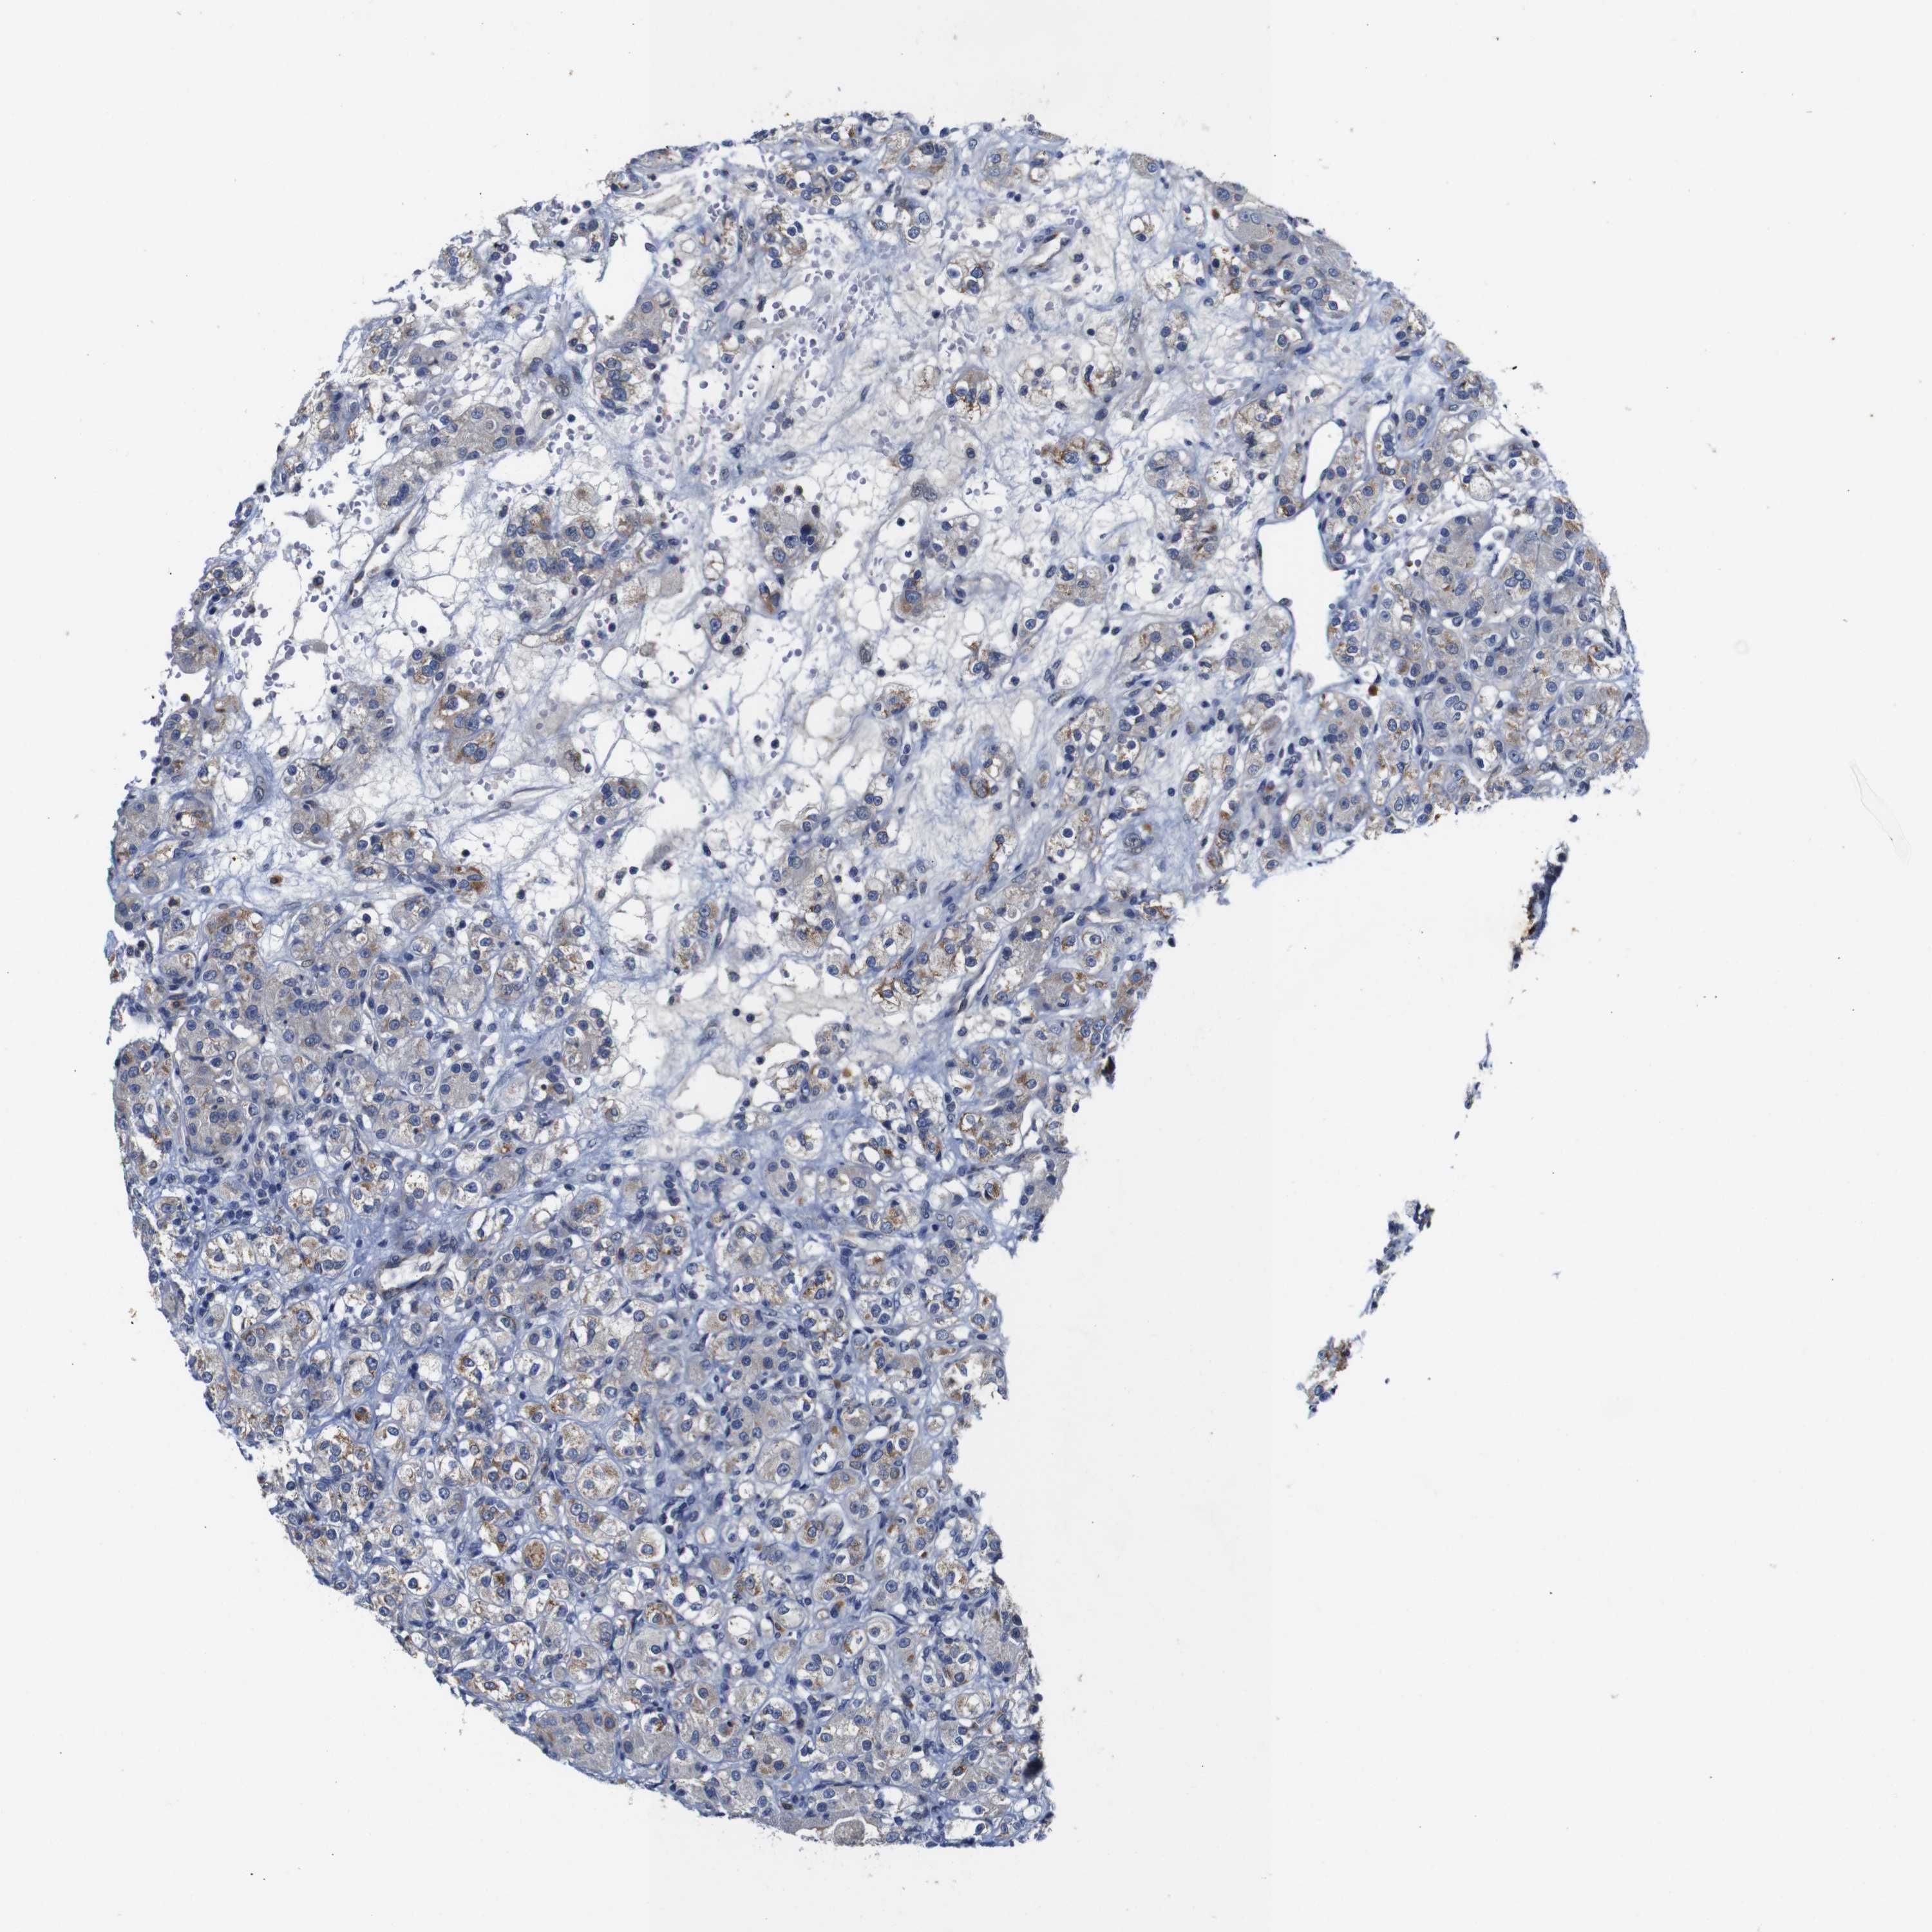

KIDNEY RENAL CLEAR CELL CARCINOMA (TCGA) - Interactive survival scatter ploti

FURIN is potential prognostic, high expression is favorable in Kidney Renal Clear Cell Carcinoma (TCGA)

Best expression cut offi

: 28.29

Average pTPM 37.4

Number of samples 521